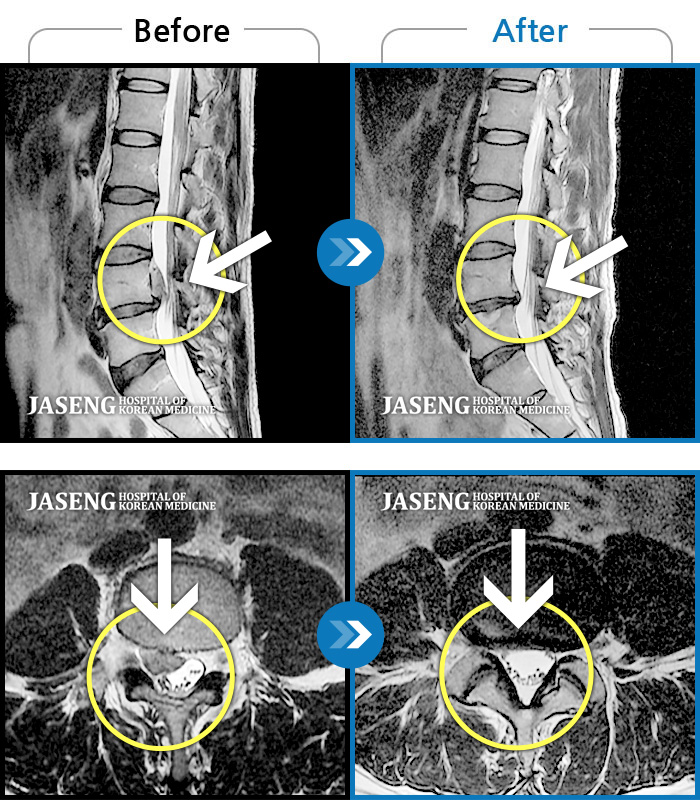

MRI 치료사례

허리통증 및 우측 하지 방사통